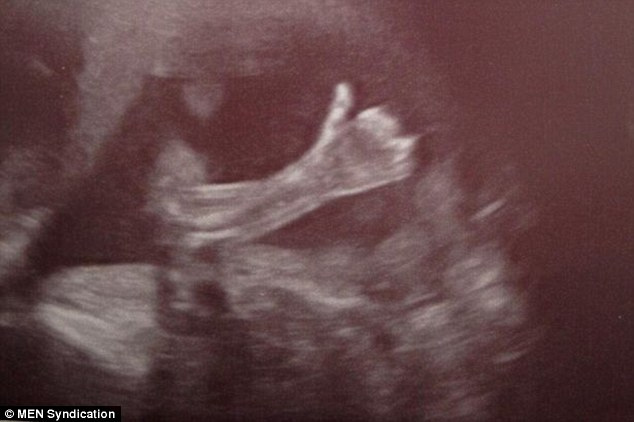

«¡Ey!, mamá y papá, por acá todo bien»: una ecografía de 20 semanas

El Daily Mail trae una de esas historias «tan suyas». Paul Schofield y Cheryl Stevenson, matrimonio treintañero presenciaba la ecografía de las 20 semanas, la imagen de su segundo hijo. LSN también se hace eco.La criatura les «regaló» un ok con el pulgar hacia arriba cuando era movida para poder determinar el sexo. Parecía decir, «no fastidien, por acá todo bien». Las enfermeras del Saint Mary de Manchester dijeron a la pareja, que estaba tronchada de risa, que nunca habían visto una imagen así.